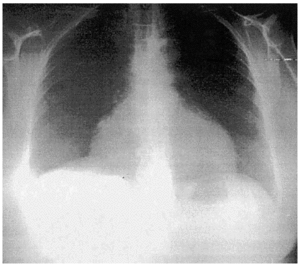

Mujer de 49 años con antecedentes personales de HTA y enfermedad pélvica inflamatoria sin secuelas. Ingresa por dolor abdominal, nicturia y edemas en miembros inferiores de 2 meses de evolución. En la ecografía realizada se apreció una masa abdominal de gran tamaño compatible con mioma uterino. Se intervino de forma programada con histerectomía total ampliada. Dos días después desarrolló hipotensión arterial, oliguria y marcado aumento de los edemas, por lo que finalmente fue preciso su ingreso en UCI. Destacaban signos de bajo voltaje en el ECG, mínima cardiomegalia y ligero derrame pleural derecho en la radiografía de tórax (figs. 1 y 2). Se realizó ecocardiografía transesofágica de urgencia donde se objetivó una masa en la aurícula derecha de 3,7 ×7 cm, de consistencia heterogénea, con punto de implantación en zona inferior del septo interauricular, que invadía el ventrículo derecho y ocupaba la mayor parte del anillo valvular auriculoventricular (fig. 3). La interpretación ecocardiográfica fue de trombo intracardíaco o mixoma auricular derecho. La paciente se intervino quirúrgicamente y se confirmó este último diagnóstico.

Figura 3.